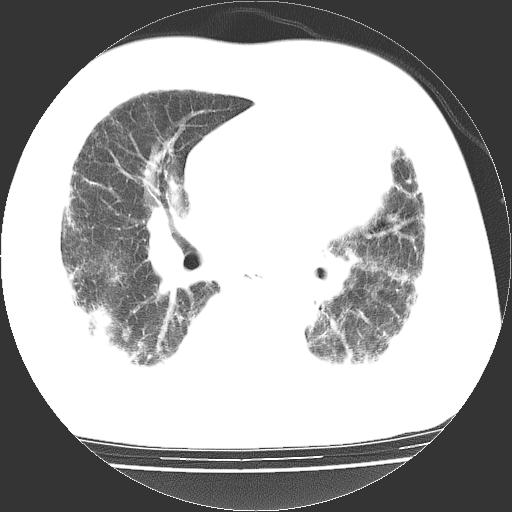

男,68岁,咳嗽、胸闷、发烧三天,查体:双肺散在湿罗音。

首先考虑特发型肺间质纤维化;两侧少量胸腔积液。

依据:1、两肺广泛条索状、网格状、蜂窝状改变。

1.双肺间质纤维化并感染;

2.双肺慢支炎肺气肿;

3.支扩并感染;

4.肺原性心脏病;

5.双侧胸腔少量积液;双侧胸膜增厚。

双肺多发条索状、网格状及小灶状密度增高影。考虑慢支合并感染.间质纤维化,双侧少量胸腔积液

两肺广泛条索状、网格状、蜂窝状改变。肺间质纤维化,肺心病,双侧胸腔积液